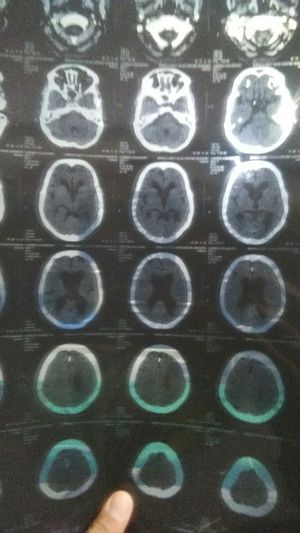

A 75 year old woman is a sudden onset giddiness and unble To speak. Admit that ICU department And complain... weakness RT. LL known case of HTN on Treatment.. No H/o DM. No H/O Trauma... And Examination Patient is altered sensorium GCS E4V2M5 Pupils BERL...... RT. LL reduced Movement  ?aphasia

A CT Head is performed what is the most likely diagnosis

the ventricles are quite dilated could point towards hydrocephalus, i cant see of there is a stroke as the image isnt very clear